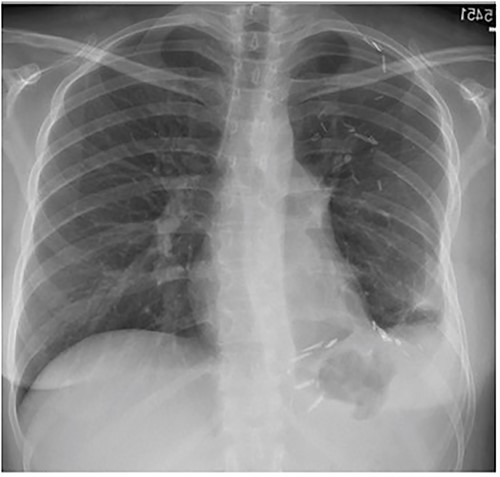

The following day a double thoracotomy was performed at the fifth and eighth intercostal space via single oblique skin incision, due to the expansion of the tumor from the left apex to the diaphragm. This allowed satisfactory exposure of the upper and lower aspects of the tumor, with the mass being delivered from the chest through the eighth interspace opening. The upper and lower lobes of the left lung were able to expand successfully. The tumor measured 22 × 26 × 11 cm, weighing ~10 lbs. The patient’s left lung expanded almost fully, and she was discharged one week post-op. At 2-month follow-up visit patient reports mild discomfort during strenuous movement/heavy lifting but denies any shortness of breath (Fig. 4).

Frontal chest radiograph 2 months after resection with near-complete left lung expansion.